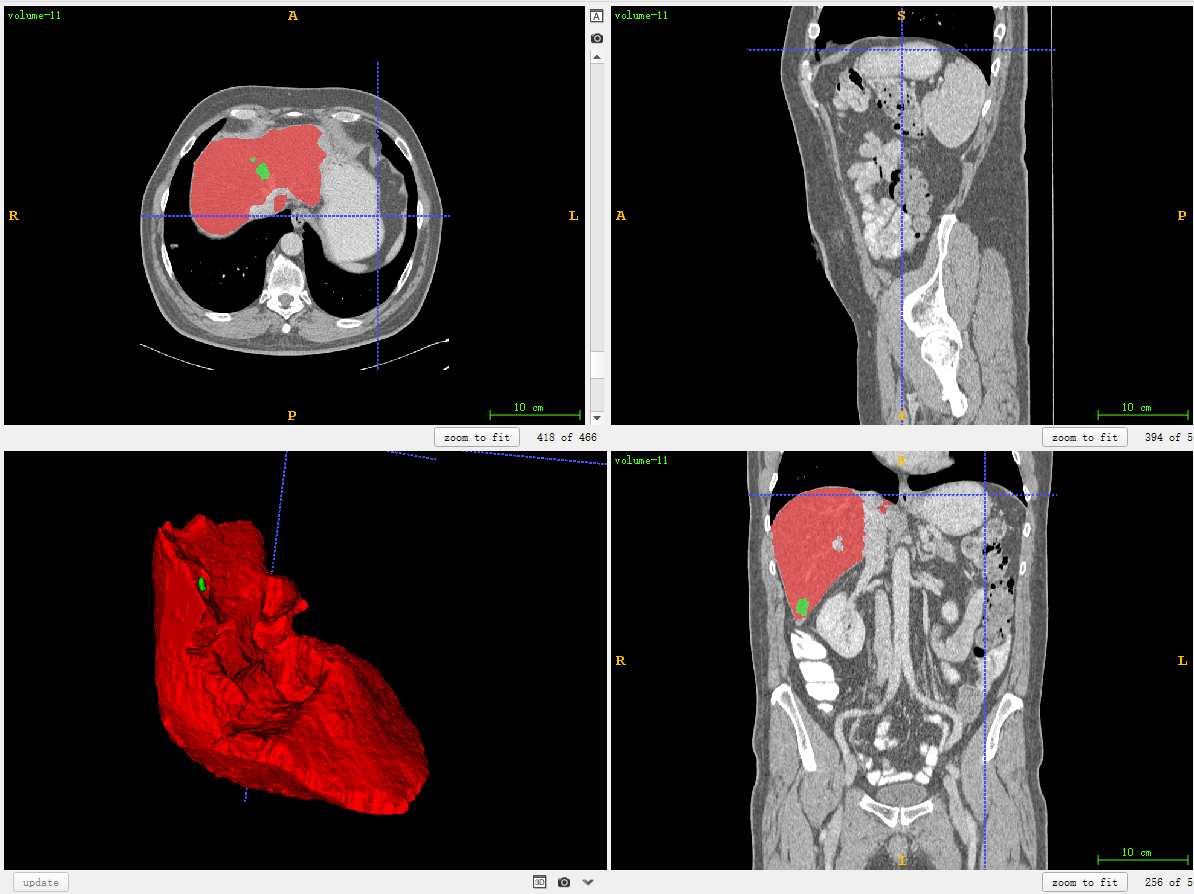

plt.imshow(data1[100,:,:]) # 对第100张slice可视化

plt.show()输出结果:

['volume-0.nii', 'volume-1.nii', 'volume-10.nii', 'volume-11.nii',...

volume-11.nii (466, 512, 512) 232.0表明该数据shape为(466,512,512),注意对应的顺序是z,x,y。z其实是slice的索引。x和y是某一个slice的宽和高。

z索引为100的plot结果:

同一个slice在ITK-SNAP可视化结果(注意这里(x,y,z=(256,256,101)),因为itk-snap默认从1开始索引):

可以发现,上下两张x轴一样但y轴方向上下翻转了,这是由于matplotlib显示方式不同,但是不会出现读取数据对不齐的问题。